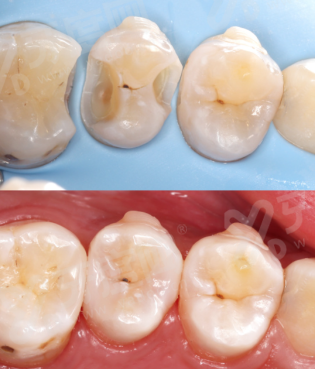

√ 淮南安美口腔所用的奥齿泰种植体可以提供多种种植体系统,适用于不同的临床需求,包括标准种植体、窄直径种植体、短种植体等,满足不同患者的解剖结构和治疗需求。

√ 士卓曼适用于单颗牙缺失、多颗牙缺失乃至全口无牙颌的修复,同时,士卓曼提供多样化的修复组件,确保修复成效既美观又功能性强。

2、治疗方案多样化:淮南安美口腔使用高质量的种植体材料,提供个性化的治疗方案,能够根据患者的具体情况和需求,选择最适合的种植方案,确保治疗成效既美观又实用。